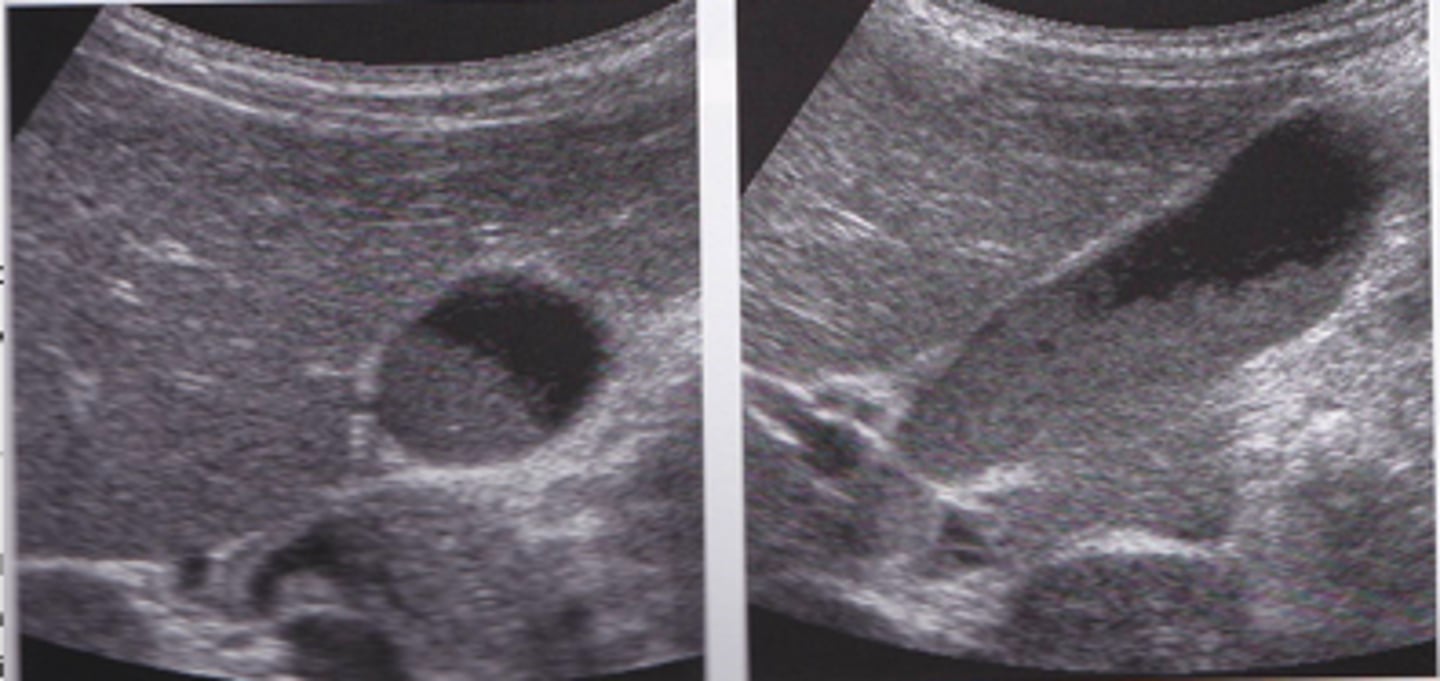

Cholelithiasis sonographic findings

- mobile, echogenic structure within GB lumen that produces posterior shadowing

-WES sign if completely filled with stones

-change in patient position that shows movement

-some stones may adhere to the wall and not cause shadow- twinkle artifact may be used to differentiate b/w a small stone and polyp:

-twinkle occurs posterior to a strong, granular surface like crystals or calcifications